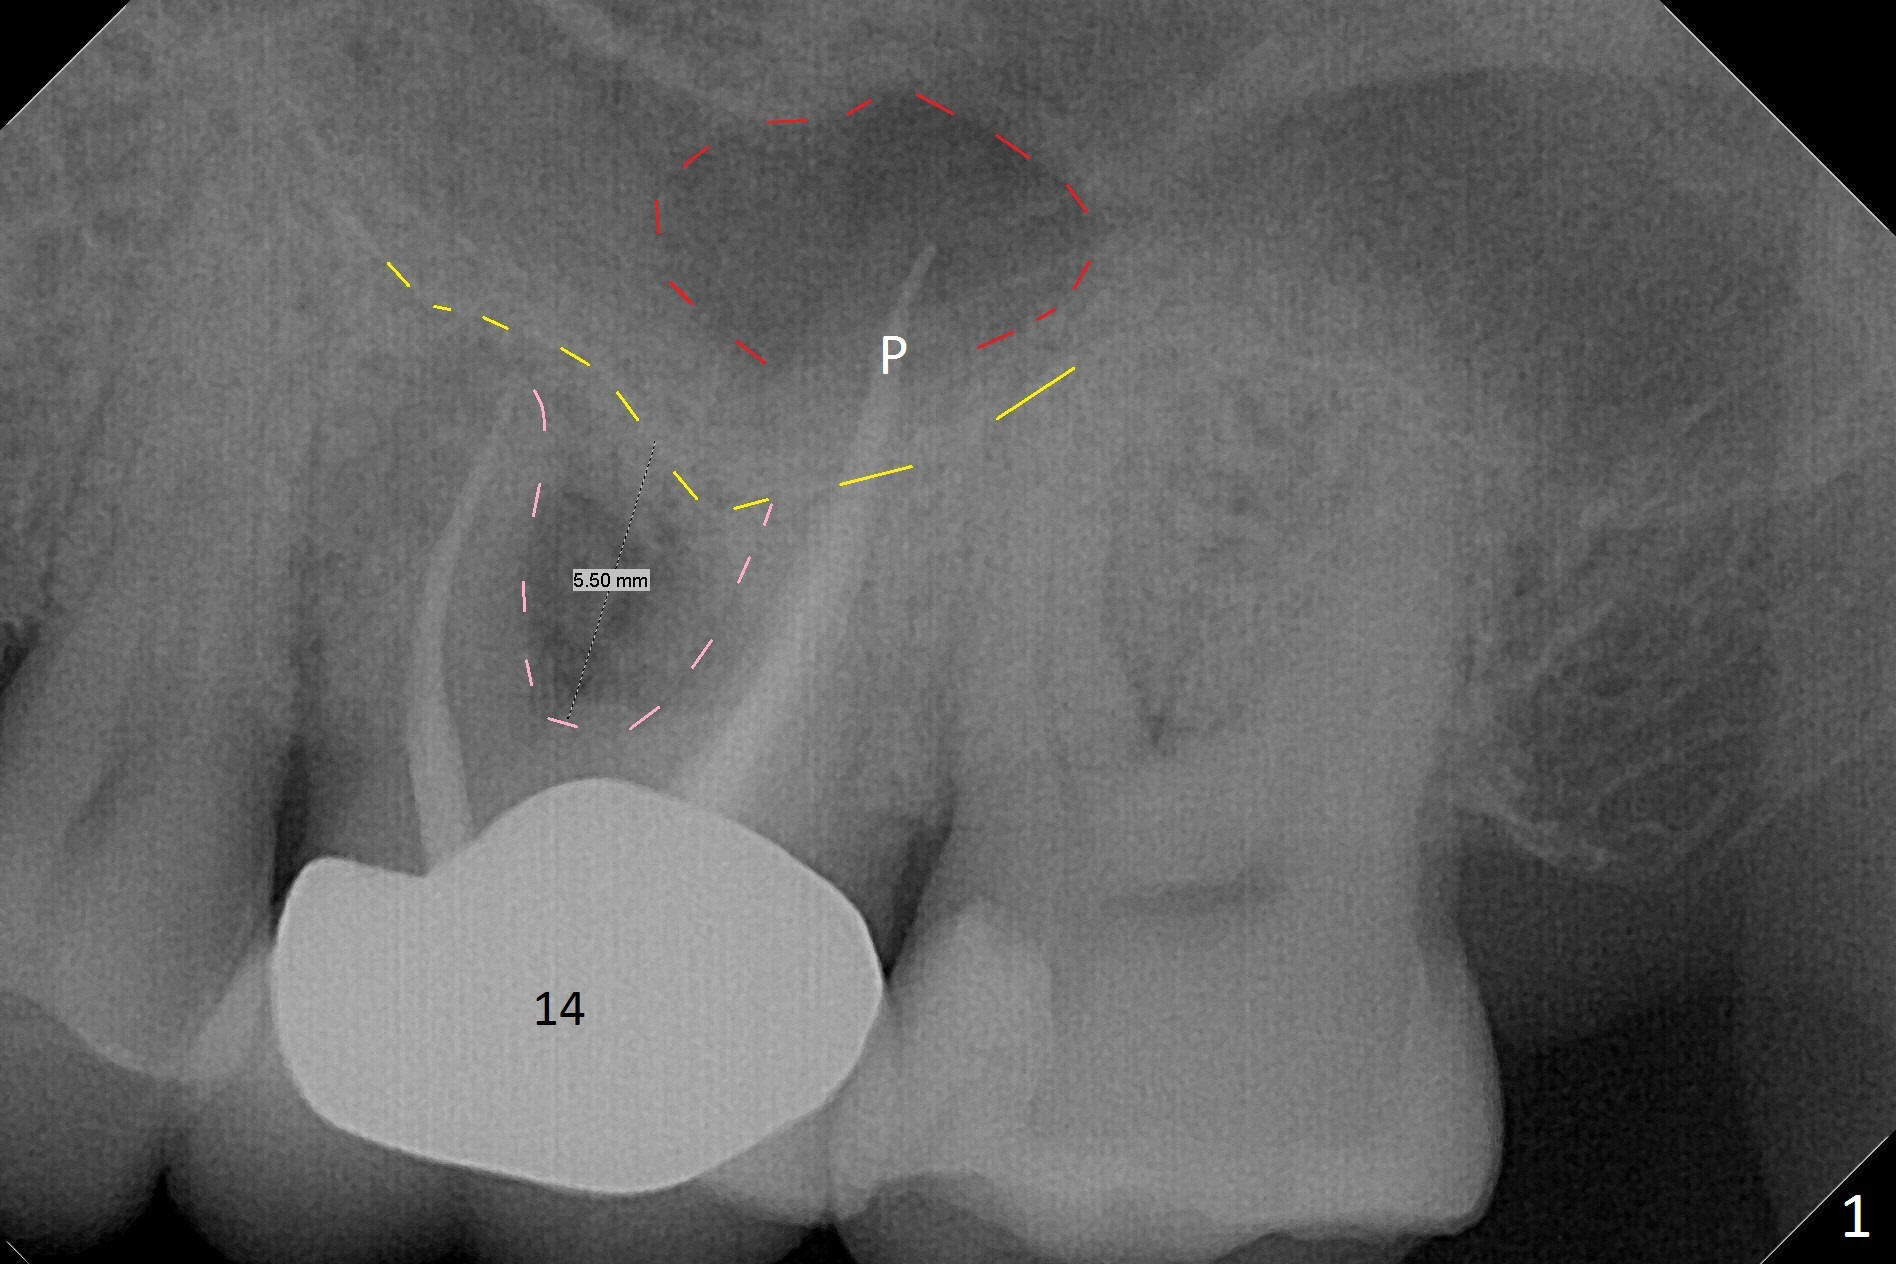

What is unclear preop is the large periapical radiolucency (Fig.1 red dashed line) of the palatal root (P) of the tooth #14.  When the tooth is extracted, it is difficult to remove granulation tissue from the palatal apical socket, which is enlarged (Fig.2 (impression of sockets),3).   The small dimension of the septum (~4x5 mm (Fig.1 pink) is also unrecognized preop, which leads to sinus perforation when 4.8 mm Magic Drill is used.  In spite of use of PRF plug and membrane, allograft does not stay in the osteotomy after placement of 4x11 mm dummy implant or 5 mm tap drill (Fig.4 for 9 mm).  Finally a 5.5x7 mm IBS implant is placed with 30 Ncm (Fig.5).  After placement of Osteogen plug in the apical portion of the sockets, allograft/Osteogen is placed in the remaining sockets (Fig. 5 *).  The latter is partially contained by a 6.5x4(3) mm abutment (A) and ultimately by an immediate provisional.

To avoid sinus membrane perforation, the initial osteotomy should be coronal to the sinus floor by 1 mm.